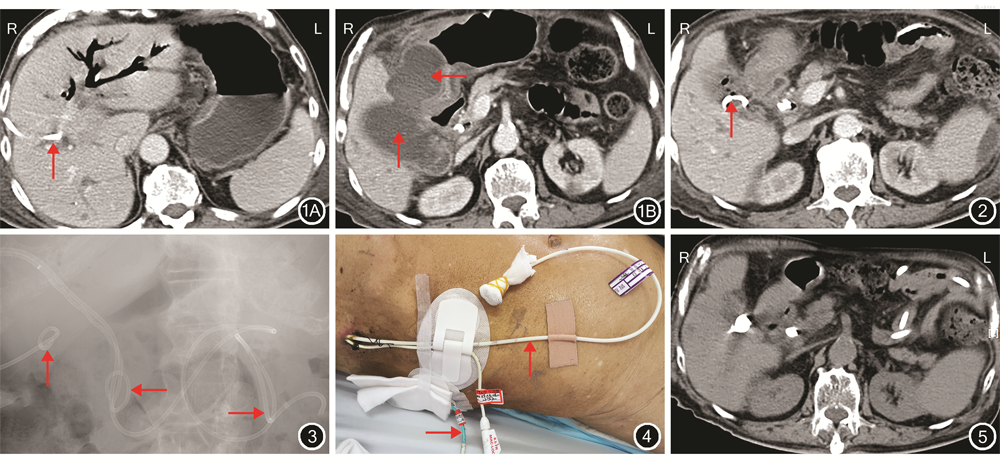

入院体格检查:体温39.5 ℃,脉搏118次/min,呼吸26次/min,血压84/69 mmHg(1 mmHg=0.133 kPa),皮肤、巩膜无黄染,浅表淋巴结未触及肿大,口唇无发绀,腹平坦,未见胃肠型及蠕动波,无腹壁静脉曲张,全腹部轻压痛,有轻度反跳痛和肌紧张,腹膜刺激征阳性,肝脾肋下未触及,移动性浊音阳性,未触及明显腹部包块,肠鸣音减弱,双下肢中度浮肿。入院辅助检查:WBC 38.7×109/L,中性粒细胞占95.1%,C反应蛋白为205.9 mg/L,TBil为48 μmol/L,Cr为148 μmol/L,Alb为20 g/L。腹部CT检查结果显示:肝内胆管积气、胆囊十二指肠瘘可能,未见胆囊结石及胆管结石(图1)。微型营养评价法营养状况评分为3分。

病人及家属均签署知情同意书。病人于2020年6月18日行PTGD(图2),术后第1天,PTGD管引流出300 mL脓液,之后持续引流出胃液和肠液,为300~500 mL/d,最终确诊为胆囊十二指肠瘘。

在抗休克、抗感染及PTGD治疗后,病人感染逐渐控制,腹膜炎体征消失,发热症状逐渐好转,于2020年7月1日在DSA下经鼻置入空肠营养管,但反复尝试营养管无法进入十二指肠以远部位,置管失败。病人年龄较大,心脏射血分数仅为33%,无法耐受胃镜操作,最终通过DSA,经PTCD窦道成功置入空肠营养管1根,即空肠营养管与PTCD引流管经同一通道进入肠道(图3,4),经空肠营养管注入肠内营养液(笔者单位营养科配置)约2 000 mL/d,总热量约1 800 kcal/d。病人经积极治疗后病情逐渐稳定,血常规、C反应蛋白、肝肾功能恢复正常,Alb逐渐回升至32 g/L。

PTGD术后4个月,随访时病人病情平稳,微型营养评价法营养状况评分上升至7分,体质量由69 kg增长至74 kg。PTGD管引流液逐渐减少(10 mL/d、引流液呈淡黄色),上腹部CT检查结果显示瘘口闭塞(图5)。病人口服清水500 mL/d,PTGD管引流液未见增多,改为流质食物,引流液仍未见增多,间接判断瘘口闭塞,遂予拔除PTGD管及PTCD窦道内的空肠营养管。病人逐渐改为软食,未再出现胆道感染症状。